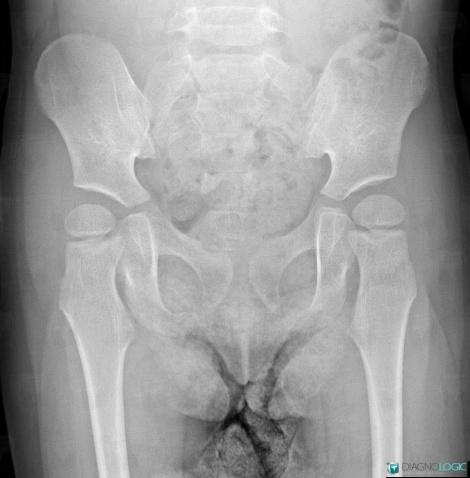

Coxa valga, Femur - Proximal part, X rays

- Diagnosis Coxa valga, Location(s) Femur - Proximal part, with gamuts